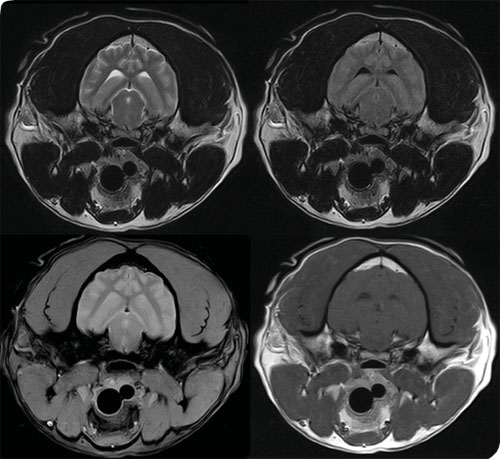

高品质成像

宠物超导磁共振可同时使用两个射频接收线圈的磁共振系统。该技术提高了图像质量,同时使兽医可以更容易进行病症诊断。通过增加材料层数实现的3D打印也被用在双线圈系统中。

成都造的宠物超导磁共振正在给国宝大熊猫做影像诊断